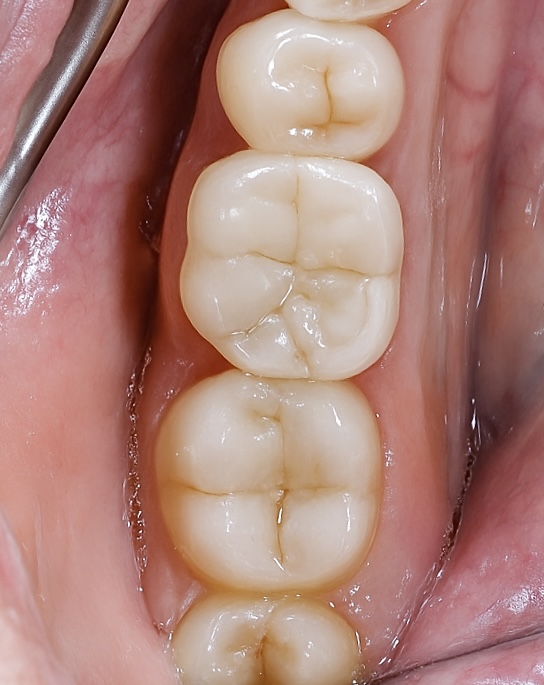

- Clinical: Smooth marginal adaptation, perfect interproximal contacts, and natural optical transition under occlusal light.

- Follow-up: Patient asymptomatic; no postoperative sensitivity; occlusal harmony maintained.

5️⃣ Final intra-oral occlusal integration